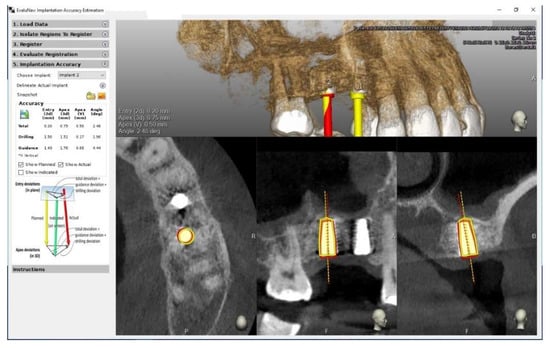

The postoperative CT scans provided information about the actual position of the implants and allowed for a comparison of the deviation between the planned implant position and the achieved position of the inserted implant. For this purpose, the EvaluNav (ClaroNav, Toronto, ON, Canada) software application, merged into the Navident system, was used. After loading and recording the preoperative and postoperative scans, the exact position of each implant was detected on the postoperative CT image and then compared with the planned position on the preoperative scan, as in Figure 5. If there was a discrepancy in the marking of a particular implant, the marking was modified manually.

Figure 5. Comparison between planning (yellow) and actual implant position (red) based on preoperative and post-operative CBCT scans.